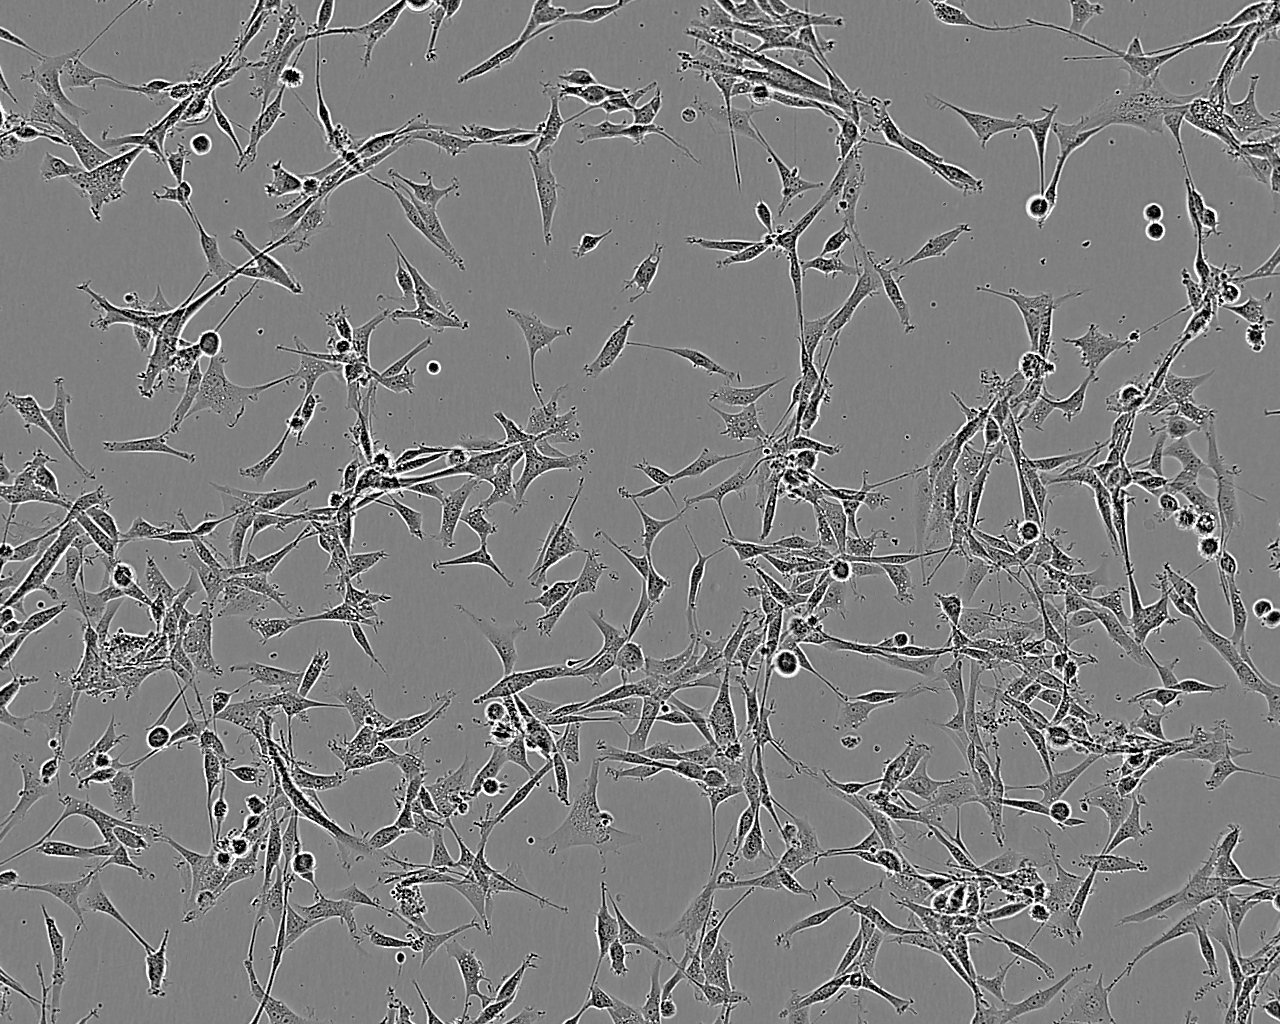

细胞形态:上皮细胞样

细胞生长:贴壁

细胞生长特性:悬浮生长